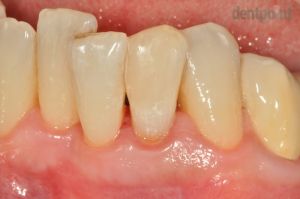

Fémmentes korona és ínyrecesszió fedés

Hölgy páciensünk metszőfogát fémmentes koronával tettük esztétikusabbá illetve visszahúzódott fogínyét ínyrecesszió fedéssel korrigáltuk.

2) Elszíneződött metszőfog